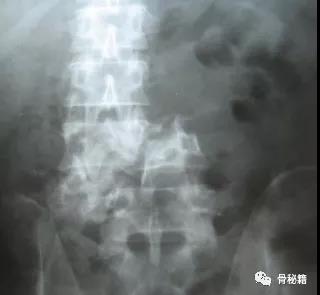

高能量损伤造成的脊柱骨折前后脱位是脊柱骨折复位的难点和要点

前后移位